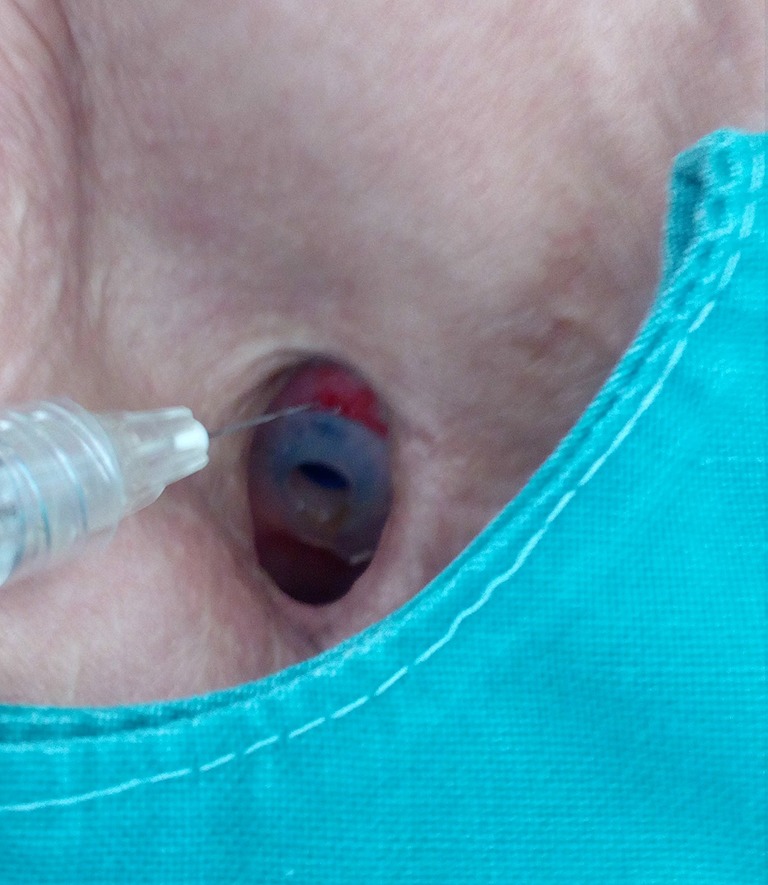

Figure 1.

Injection of Algeness 2.5% around a provox prosthesis after total laryngectomy, to manage a periprosthetic leakage of liquids, saliva and food.

Figure 2.

Immediate volumizing effect at the cranial aspect of the prosthesis, with direct improvement of the treated leakage.

A swallowing test is performed in order to locate the leakage. If saliva or fluid flows from the central part of the Provox, replacement is indicated. In cases of a peripheral leakage (around the Provox) or mostly at the upper part of the Provox, injections with fillers can solve the problem easily Algeness proved to be an excellent choice of filler for this indication (Figure 1). Immediately after the injection of a small amount, mostly 0.3–0.5 mL of Algeness 2.5%, the result can be controlled with a new swallowing test with some liquid as water, milk, etc. (Figure 2). Dysphagia or pain symptoms were not reported and all patients experienced an improvement in their quality of life, having the opportunity to drink and eat without the possible danger of a pneumonia. Moreover, all patients avoided an unpleasant Provox replacement and reported being symptom free from 5 to 13 months. Prior to injection tracheal reflexes and coughing can be controlled with the use of xylocaine spray directly on the Provox area.